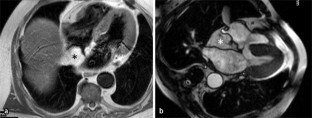

Abb. 4

19. Grothoff M, Pachowsky M, Hoffmann J et al (2012) Value of cardiovascular MR in diagnosing left ventricular non-compaction cardiomyopathy and in discriminating between other cardiomyopathies. Eur Radiol 22(12):2699–2709

PubMed Central  PubMed  Article  Google Scholar